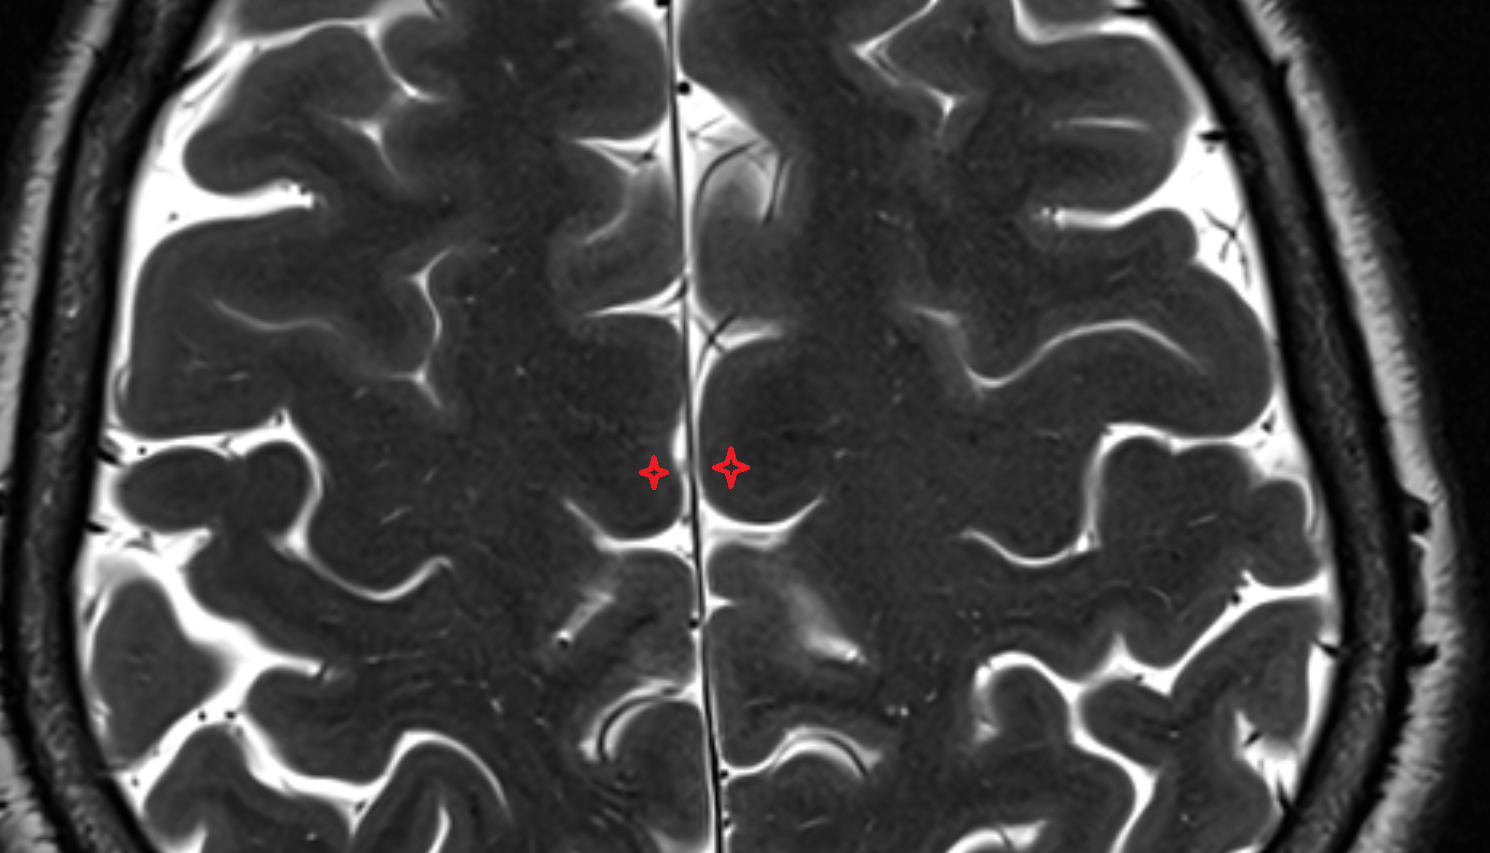

- Longitudinal cerebral fissure